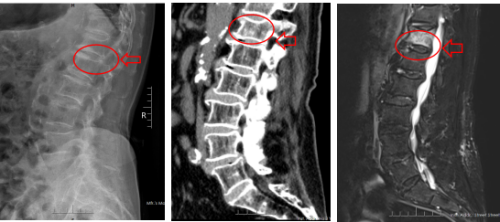

术前X线 术前CT 术前MRI